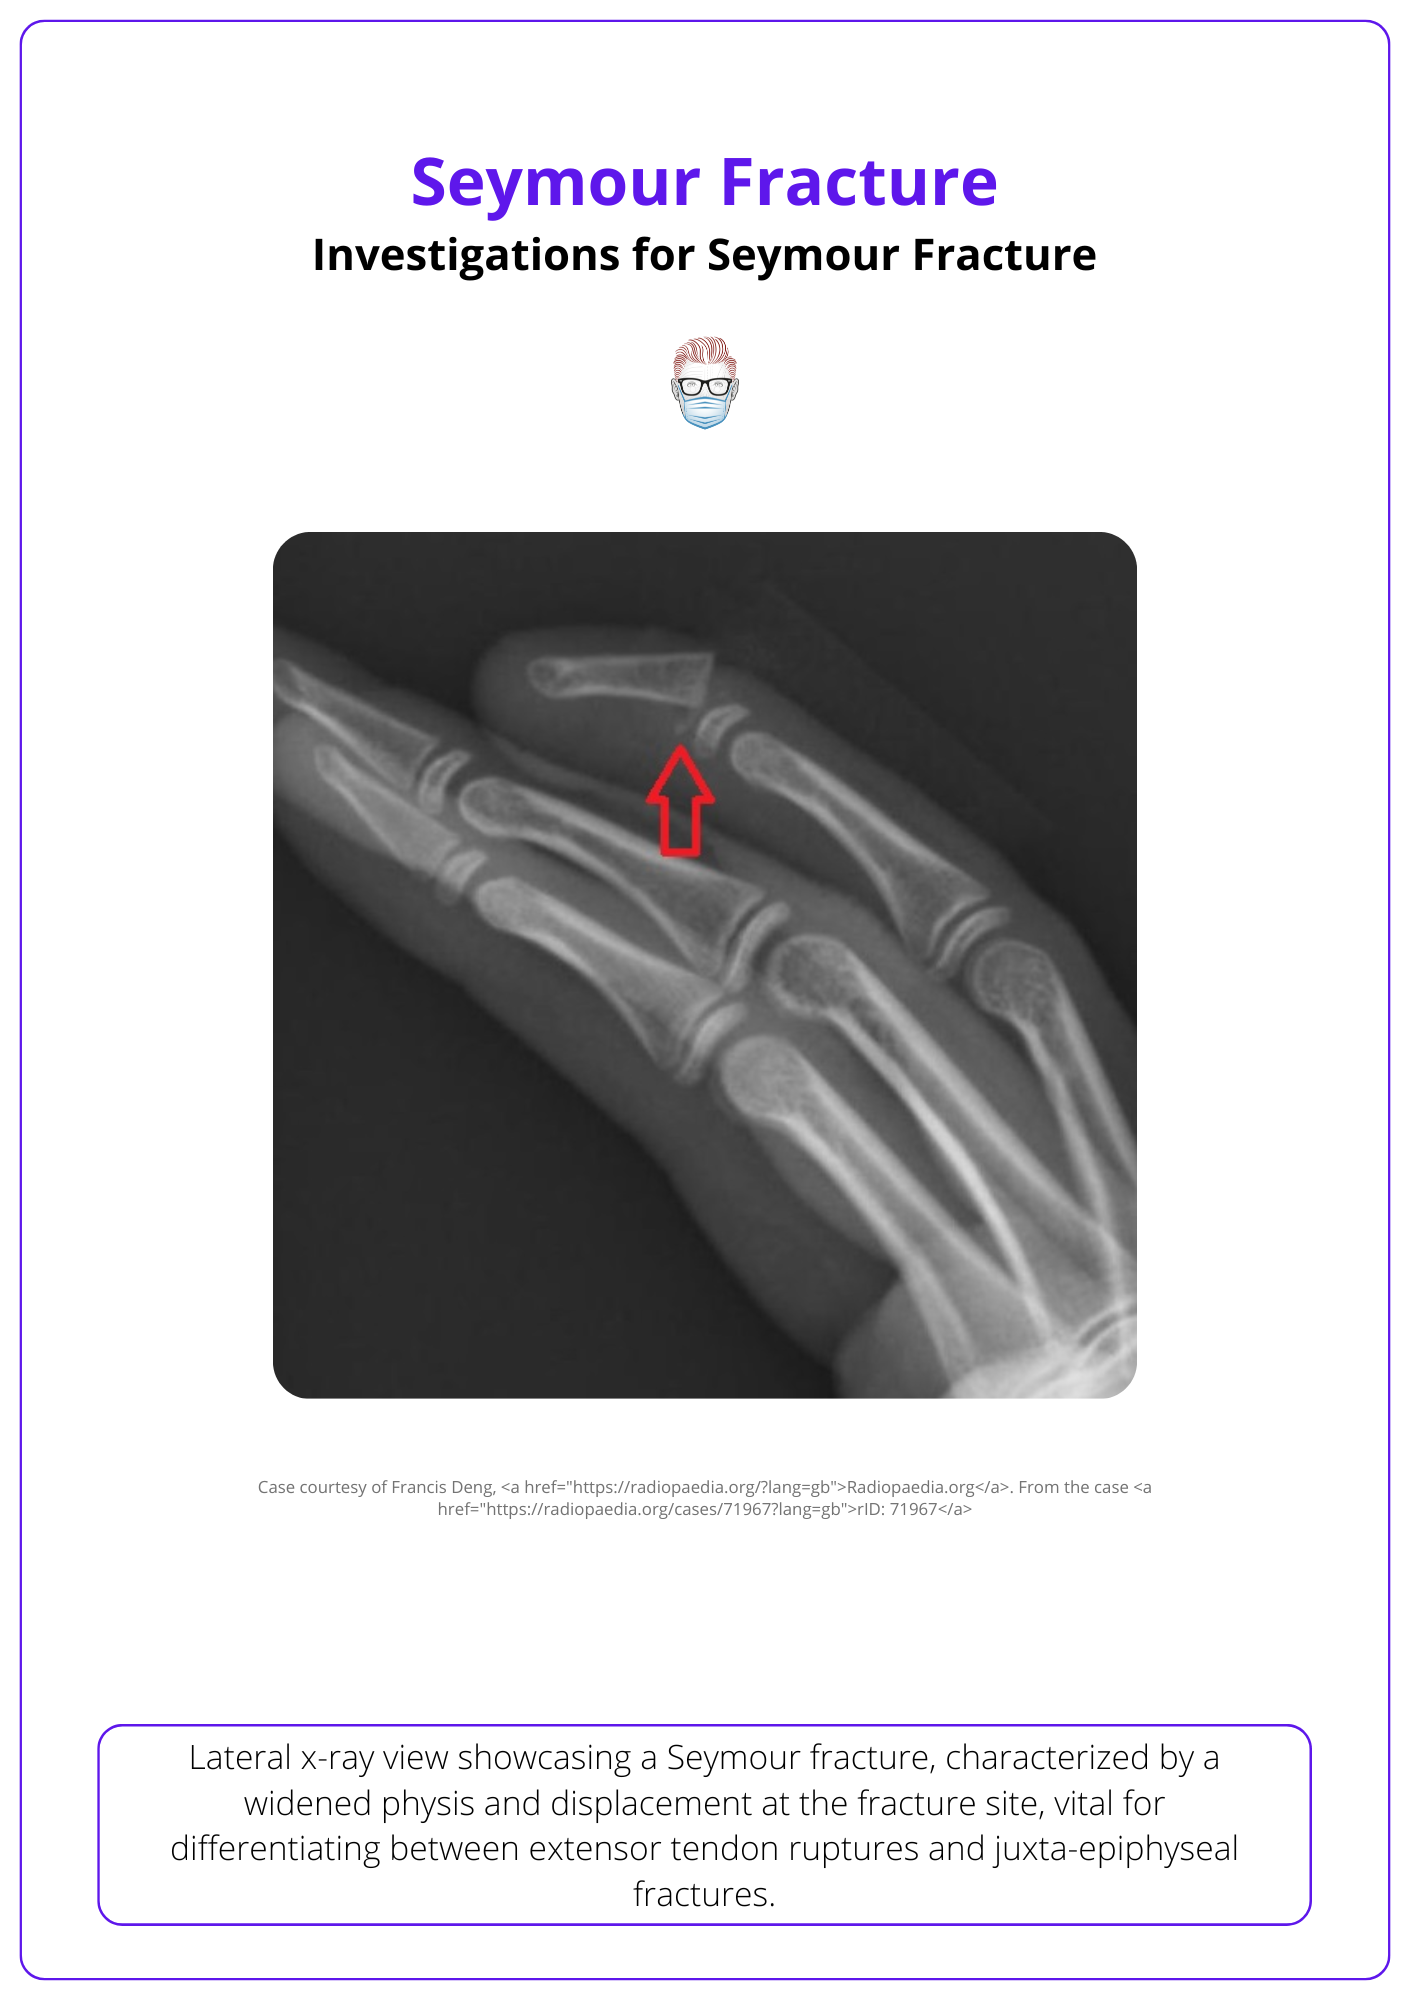

X-rays, especially the lateral view are key to identifying Seymour fractures.

The identification of Seymour fractures is key to ensuring adequate and appropriate treatment. X-ray is the imaging modality of choice, key radiological findings are:

- Posteroanterior: may appear normal.

- Lateral: widened physis or displacement between epiphysis and metaphysis. They may also be a flexion deformity at the fracture site.

The image below illustrates Seymour fracture on the lateral view of an X-ray.

A lateral x-ray distinguishes between an extensor tendon rupture and a juxta-epiphyseal Seymour fracture.